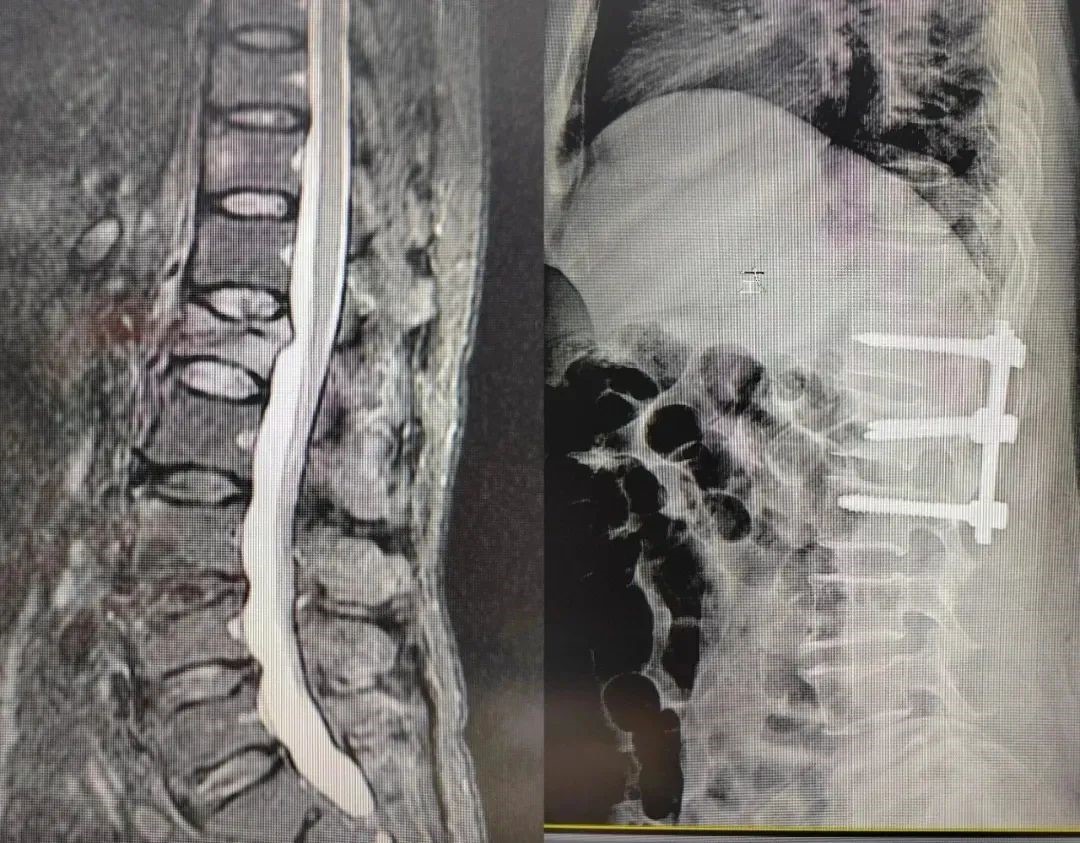

病例三

59岁女性患者,因出现腰背部疼痛,伴屈伸活动受限,床上翻身、久站后疼痛加重明显,特来医院就诊,骨二科团队经辅助检查诊断为腰1椎体压缩性骨折,需要尽快进行手术。

骨二科团队查看病人后,组织讨论中提到:一是患者腰1椎体后缘不完整,注射骨水泥发生渗漏的风险极高;二是考虑患者年龄不算太大,不宜行椎体成形术;经过讨论,骨二科团队决定实行经肌间隙入路腰1椎切开复位内固定术,这个方案的好处在于:骨折复位好、手术损伤小、术后恢复快。

骨二科团队告知患者及家属病情及治疗方案,向患者及家属详细交代手术危险性及并发症,随后在手麻科的保驾护航下,骨二科团队在全麻下行腰1椎体压缩性骨折微创切开复位内固定术,手术顺利,患者术后恢复良好,目前已出院。